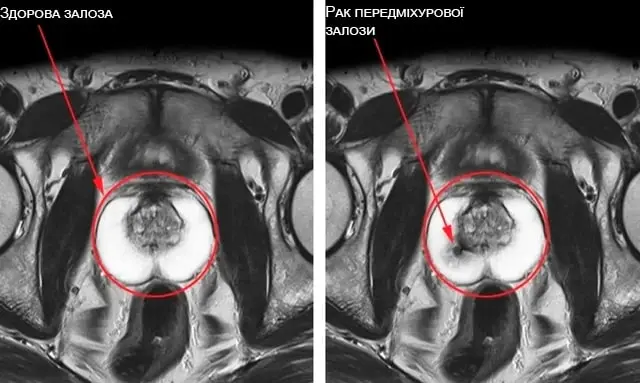

Хвороби, пов'язані з передміхуровою залозою: простатит, аденома, рак простати (протягом 3-4 років) |

Лікує простатит та аденому простати

Практично всі проблеми із простатою у чоловіка виникають через застій насіннєвої рідини. Так як Fenix повертає секс в життя чоловіка, усувається застій. Крім того, Fenix містить багато активних компонентів, що впливають на тканину залози. Fenix – один із найкращих препаратів не тільки для відновлення потенції, а й лікування простатиту, а також попередження раку простати.

Рак простати розвивається в усіх імпотентів

протягом 8-12 років. Єдина можливість його уникнути - це займатися сексом до

старості (як мінімум до 80 років)